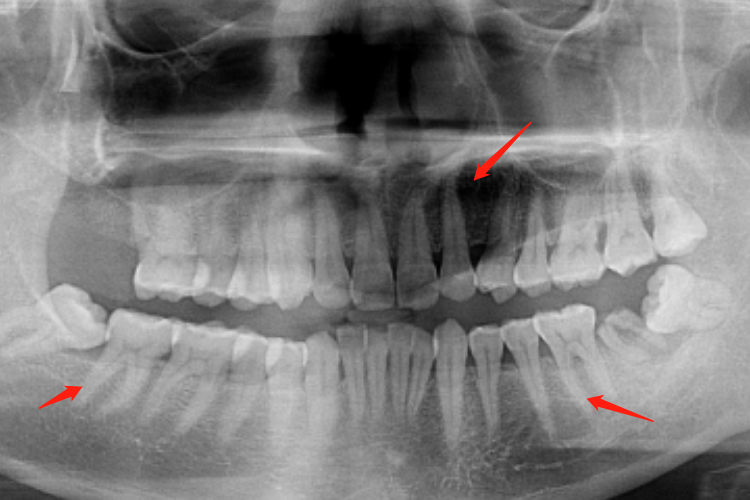

正常牙根因咀嚼力的大小和功能不同,牙根数目和大小也不相同。不论乳牙还是恒牙,其上、下前牙和第一、第二前磨牙通常为单根牙,上颌第一前磨牙多为双根牙,磨牙通常为多根牙。

上颌第一、第二磨牙三根,即近中颊侧根、远中颊侧根及腭侧根;下颌第一、二磨牙为双根,即近中根和远中根;有时下颌第一磨牙为三根,即远中根,再分为颊、舌根。上、下颌第三磨牙的牙根变异较多,常呈融合根。

牙根在牙槽窝内的稳固是保证牙冠行使其生理功能的前提,稳固的牙根又与其形态密切相关。切牙承受给力较小,多为单根。上颌切牙在咀嚼过程中承受向前、上的力,故其唇面较宽,以加强抵抗力;下颌切牙承受向内、下的力,牙根的唇面与舌面几乎相等。尖牙位于牙列的转弯处,易遭受外力,故牙根特别强大。

后牙主要承担咀嚼任务,承受力大且复杂,故其常为多根,并在牙根的近、远中面有凹陷,颌骨牙槽突嵌入此凹陷中以增强抵抗力。牙根分叉也是支持牙体得以稳固的重要因素,分叉越多,其支持作用则越强。